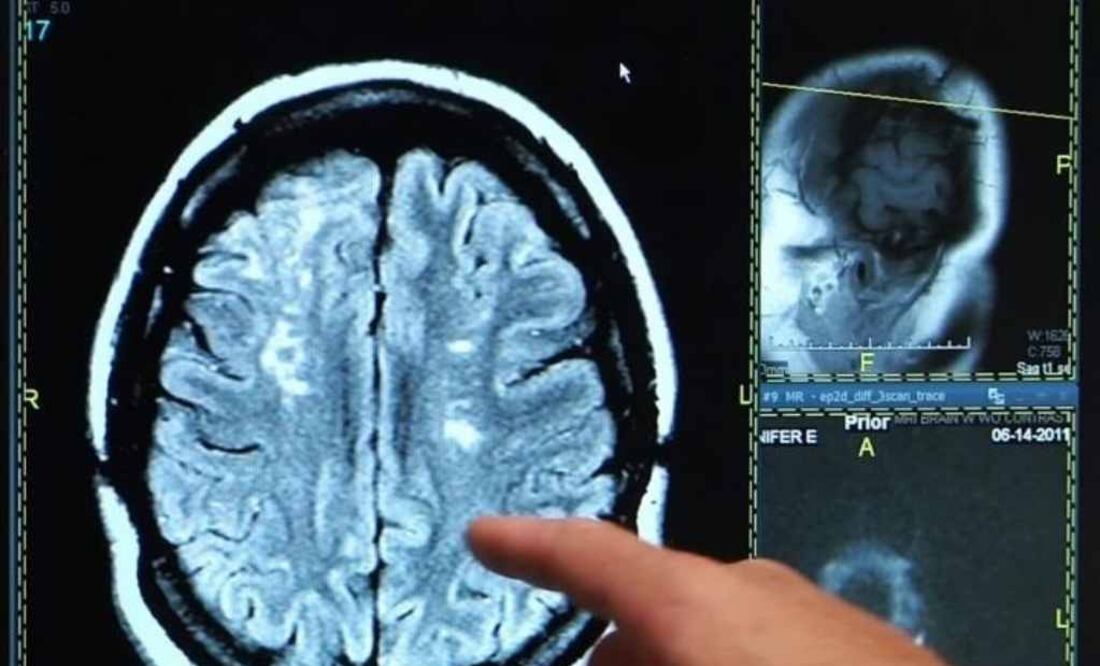

Los nacidos entre 1945 y 1954 pueden ser considerados la "generación más sana en cuanto a accidentes cerebrovasculares", según un estudio realizado por la Universidad de Rutgers, en Nueya Jersey, Estados Unidos, que encontró la incidencia más baja de ictus isquémico en este grupo de edad en los últimos 20 años.

Por el contrario, la tasa de accidente cerebrovascular es más del doble en la generación X, es decir, las personas nacidas entre 1965 y 1974, durante el mismo periodo de tiempo.

"La incidencia de accidente cerebrovascular ha disminuido considerablemente en general desde 1950, debido al avance de la medicina", afirma Joel N. Swerdel, autor principal del estudio realizado en el Instituto Cardiovascular de Nueva Jersey en la Escuela de Medicina de la Universidad de Rutgers ."Sin embargo, encontramos que la tendencia se invierte en las generaciones más jóvenes donde la obesidad y la diabetes están probablemente causando un aumento en las enfermedades cardiovasculares", añade.

Los investigadores analizaron más de 225.000 registros de datos de accidente cerebrovascular entre 1995 y 2014, separados en cinco grupos, cada uno con una edad de 10 años. El análisis, que se publica en 'Journal of the American Heart Association', encontró que las personas nacidas en los 20 años previos a 1945 y los nacidos en los 20 años posteriores a 1954 tenían mayores riesgos de accidente cerebrovascular. Sólo el grupo que ahora está entre 60 y 70 años de edad vio una reducción en la incidencia de accidente cerebrovascular durante el intervalo de años incluidos en el estudio.

"Una mayor incidencia de ictus en individuos nacidos antes de 1945 no fue sorprendente, ya que no se beneficiaron de la disponibilidad de fármacos hipolipemiantes, como las estatinas, y la terapia antihipertensiva, al igual que las generaciones más jóvenes", apunta Kostis, investigador principal del trabajo. "Sin embargo, la creciente incidencia del accidente cerebrovascular en la generación más joven --los que están entre las edades de 35 y 50 años-- es alarmante y merece más investigación".

Los investigadores atribuyen a varios factores la tendencia al alza, como la falta de adherencia al tratamiento prescrito, por ejemplo tomar medicamentos para controlar la presión arterial, y un incremento significativo en la obesidad y la prevalencia de la diabetes, ambos factores de riesgo de la enfermedad cardiovascular. Aunque MIDAS incluye datos de Nueva Jersey, los investigadores creen que la evidencia es indicativa de las tendencias en Estados Unidos.